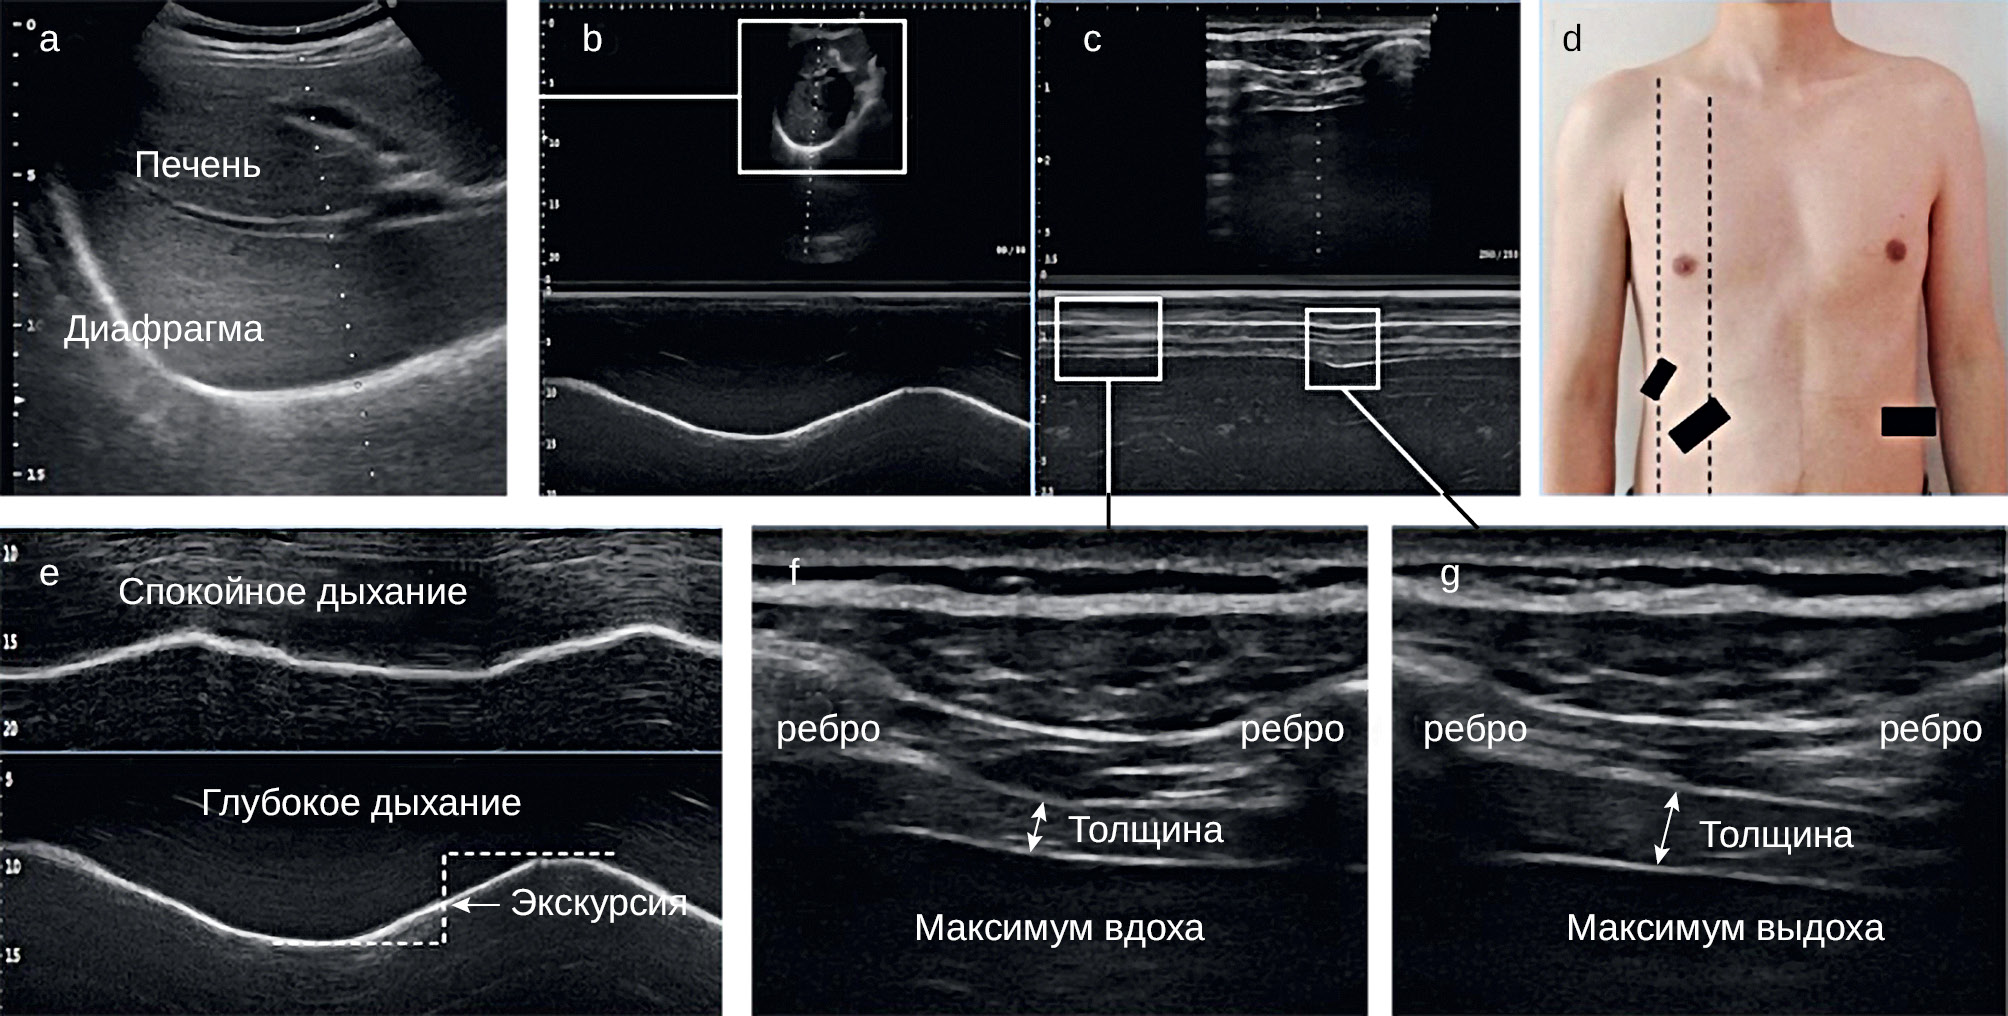

3.2.4. Ультразвуковое исследование диафрагмы

Исследование становится все более популярным среди специалистов. Метод позволяет визуализировать диафрагму, оценить ее форму и экскурсию, а также сделать измерения толщины (Tdi) и динамические оценки доли утолщения (TFdi) и экскурсии диафрагмы. Tdi и TFdi можно оценить с помощью ультразвука с высокочастотным линейным датчиком, расположенным на уровне зоны аппозиции. TFdi менее 20 % предлагается в качестве порогового значения, указывающего на наличие дисфункции диафрагмы. Существуют ограничения метода, связанные как с опытом оператора, так и с телосложением пациента. По данным ряда авторов, УЗИ диафрагмы имеет лучшую чувствительность, чем рентгеноскопия для обнаружения односторонней дисфункции диафрагмы, другие исследования подтвердили успешное использование ультразвука для мониторинга восстановления с течением времени. УЗИ имеет меньшую точность и большую зависимость от оператора по сравнению с КТ и МРТ, однако среди визуализационных методов является наиболее доступным, комфортным и безопасным для пациента [6, 17, 18, 23–26] (рис. 5).

Рис. 5. Ультразвуковое исследование диафрагмы [6] Примечание: А — УЗИ в В-режиме, где гиперэхогенная линия соответствует диафрагме, а пунктирная линия имеет угол около 30°; В — УЗИ в М-режиме, где амплитуда движения гиперэхогенной линии соответствует подвижности диафрагмы; С — ультрасонография в М-режиме, где пунктирная линия расположена на диафрагме, а толщину диафрагмы можно наблюдать во время дыхания; D — положение датчиков, где левая пунктирная линия представляет собой переднюю подмышечную линию, а правая пунктирная линия представляет собой срединно-ключичную линию, и два больших черных прямоугольника — места расположения низкочастотных датчиков, а меньший черный прямоугольник — место расположения высокочастотного датчика; Е — ультрасонография в М-режиме, показывающая измерение подвижности диафрагмы при спокойном и глубоком дыхании; F, G — УЗИ в B-режиме, показывающее измерение толщины диафрагмы в конце вдоха и в конце выдоха.

Fig. 5. Ultrasound examination of the diaphragm [6] Note: A — B-mode ultrasonography, where the hyperechoic line is the diaphragm, and the dotted has an angle of about 30°; B — M-mode ultrasonography, where the movement amplitude of the hyperechoic line is the mobility of the diaphragm; C — M-mode ultrasonography, where the dotted line is positioned on the diaphragm, and diaphragm thickness can be observed during breathing; D — the probes position, where the left dotted line is the anterior axillary line, and the right dotted line is the midclavicular line, and the two larger black boxes are low frequency probes, while the smaller black box is the high-frequency probe; E — M-mode ultrasonography showing the measurement of diaphragm mobility during quiet and deep breathing; F, G — B-mode ultrasonography showing the measurement of diaphragm thickness at end-inspiration and end-expiration.